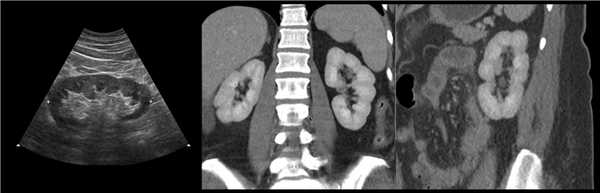

Клинический пример из второй группы. Пациент К. перенес операцию пересадки почки от живого родственного донора. Трансплантат в левой подвздошной области. Индекс резистентности в междольковых артериях составил 0,70 (рис. 5). В сегментарных артериях индекс резистентности составил 0,66 (рис. 6). Показатели жесткости паренхимы почечного трансплантата при режиме УЭСВ составили от 31,6 до 36,9 кПа (рис. 7-9).

Рисунок 7. Исследование в режиме ультразвуковой эластографии сдвиговой волны у пациента К.: жесткость паренхимы в зоне медиального края почечного трансплантата 36,9 кПа

Рисунок 8. Исследование в режиме ультразвуковой эластографии сдвиговой волны у пациента К.: жесткость паренхимы в зоне нижнего полюса почечного трансплантата 34,7 кПа

Рисунок 9. Исследование в режиме ультразвуковой эластографии сдвиговой волны у пациента К.: жесткость паренхимы у верхнего полюса почечного трансплантата 31,6 кПа

При снижении скорости кровотока и повышении индекса резистентности до 0,70 и более, как в первой, так и во второй группах, показатели УЭСВ составили от 28,00 до 39,45 кПа. Повышение жесткости паренхимы почечного трансплантата, на наш взгляд, связано с начавшимися изменениями (фиброза) в паренхиме почки. При повышении индекса резистентности более 0,70 показатели жесткости паренхимы при УЭСВ является дополнительным критерием, позволяющим оценить функциональное состояние почечного трансплантата. Ультразвуковая эластография ― новая развивающаяся методика, чувствительность, специфичность и точность которой увеличиваются при комплексном использовании с другими методами исследования. Анализ результатов проведенных исследований выявил значительные клинические возможности и перспективы применения метода ультразвуковой эластографии сдвиговой волны в оценке состояния почечного трансплантата. Полученные данные о диагностической точности метода позволяют использовать результаты в целях принятия решения о дальнейшем ведении пациента и тактике лечения [4].